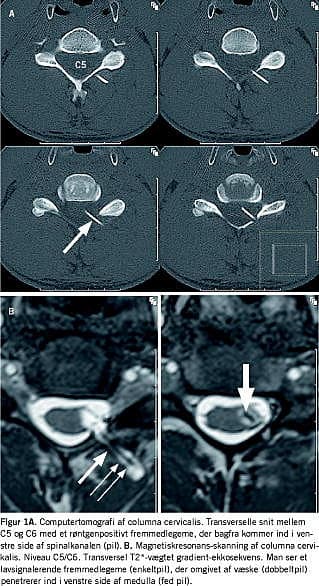

Ved en magnetisk resonans (MR)-skanning af columna cervicalis blev der påvist et ikkemetallisk fremmedlegeme, ekstra- og intraduralt, penetrerende venstre side af medulla på niveau C5/C6. Fremmedlegemet var omgivet af væske. En computertomografi (CT) (og røntgenundersøgelse - ikke vist), der blev udført for nærmere karakteristik af arten af fremmedlegemet, tydede på, at det bestod af plastik (Figur 1A og B).